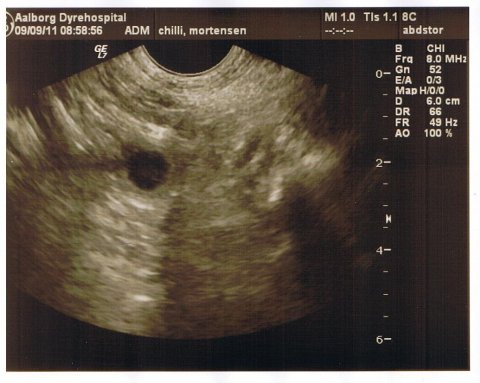

Scanning